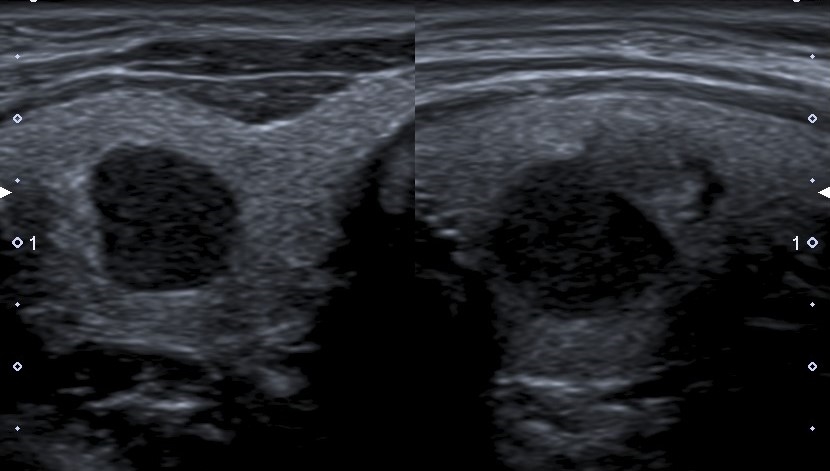

Calcificaciones

Focos ecogénicos que pueden clasificarse según su tamaño en microcalcificaciones (Fig. 15) y macrocalcificaciones (Fig. 16). Las primeras miden menos de 1 mm y no presentan sombra acústica posterior, a diferencia de las macrocalcificaciones que son mayores de 1 mm con sombra acústica posterior.

Las microcalcificaciones presentan un alto riesgo de malignidad. De hecho, algunos autores las consideran por sí solas un predictor de malignidad20, y otros sostienen que la presencia de microcalcificaciones sumado al aumento de la vascularización central y una imagen ganglionar patológica son suficientes para indicar una punción aspiración con aguja fina23.

El artefacto en cola de cometa (Fig. 17) es producido por la reverberación en los quistes coloides, que pueden confundir con microcalcificaciones. A diferencia de estas últimas, el artefacto en cola de cometa se visualiza como una línea ecogénica brillante con un triángulo o líneas ecogénicas posteriores, y se suele asociar a benignidad2.